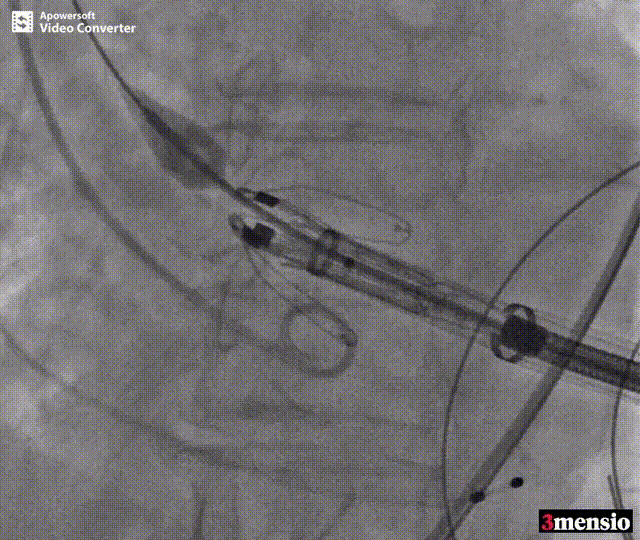

术前DSA影像图

术中释放定位键后DSA影像图

患者全麻后,于左侧心尖3-4cm处进行微创手术切口。在DSA及超声引导下,输送Ken-Valve瓣膜系统进入左心室,边调弯边推送,使得瓣膜在术中始终保持较好的同轴性,从送入输送器到瓣膜释放不足十分钟。术后即刻患者返流消失,于外科杂交手术室拔除气管插管,次日即由ICU转入普通病房。